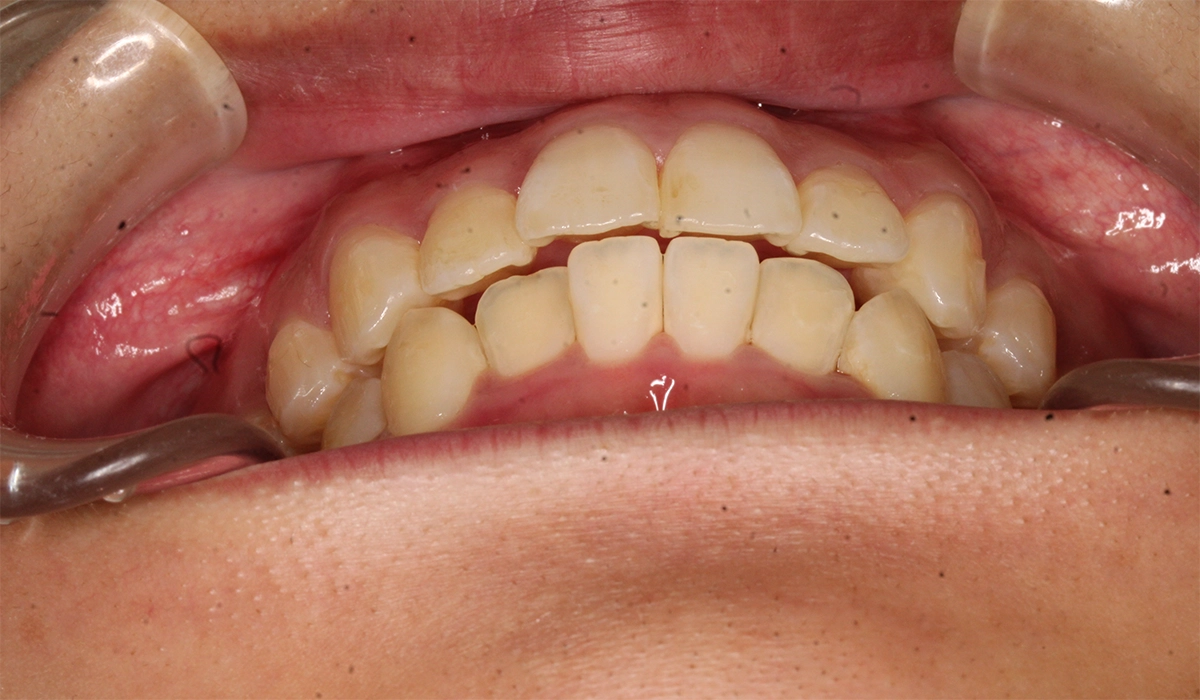

術前:正面